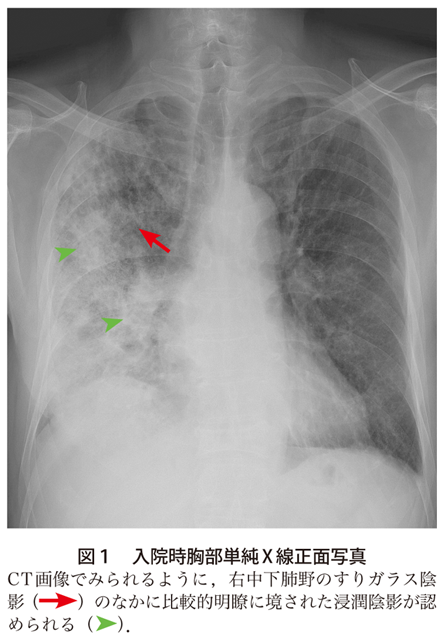

解答 解説 呼吸困難と発熱を主訴とした70歳代男性 実践 画像診断q A 羊土社 レジデントノート 実践 画像診断q A 羊土社 レジデントノート 羊土社